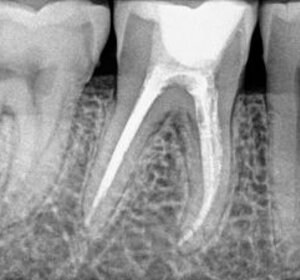

la cura consiste nella devitalizzazione - endodonzia del dente, ossia:

- viene aperto il dente fino ad arrivare alla camera pulpare: si accede alla polpa attraverso una cavità preparata sul lato masticante del dente

- Reperimento dei canali radicolari

- Misurazione della lunghezza del canale

- Strumentazione dei canali radicolari: mediante questi strumenti viene asportata la polpa infetta

- Lavaggi canalari con ipoclorito di sodio: questa soluzione permette di disinfettare e sterilizzare l’interno del dente

- Otturazione del canale mediante materiali appositi

- Ricostruzione della corona del dente